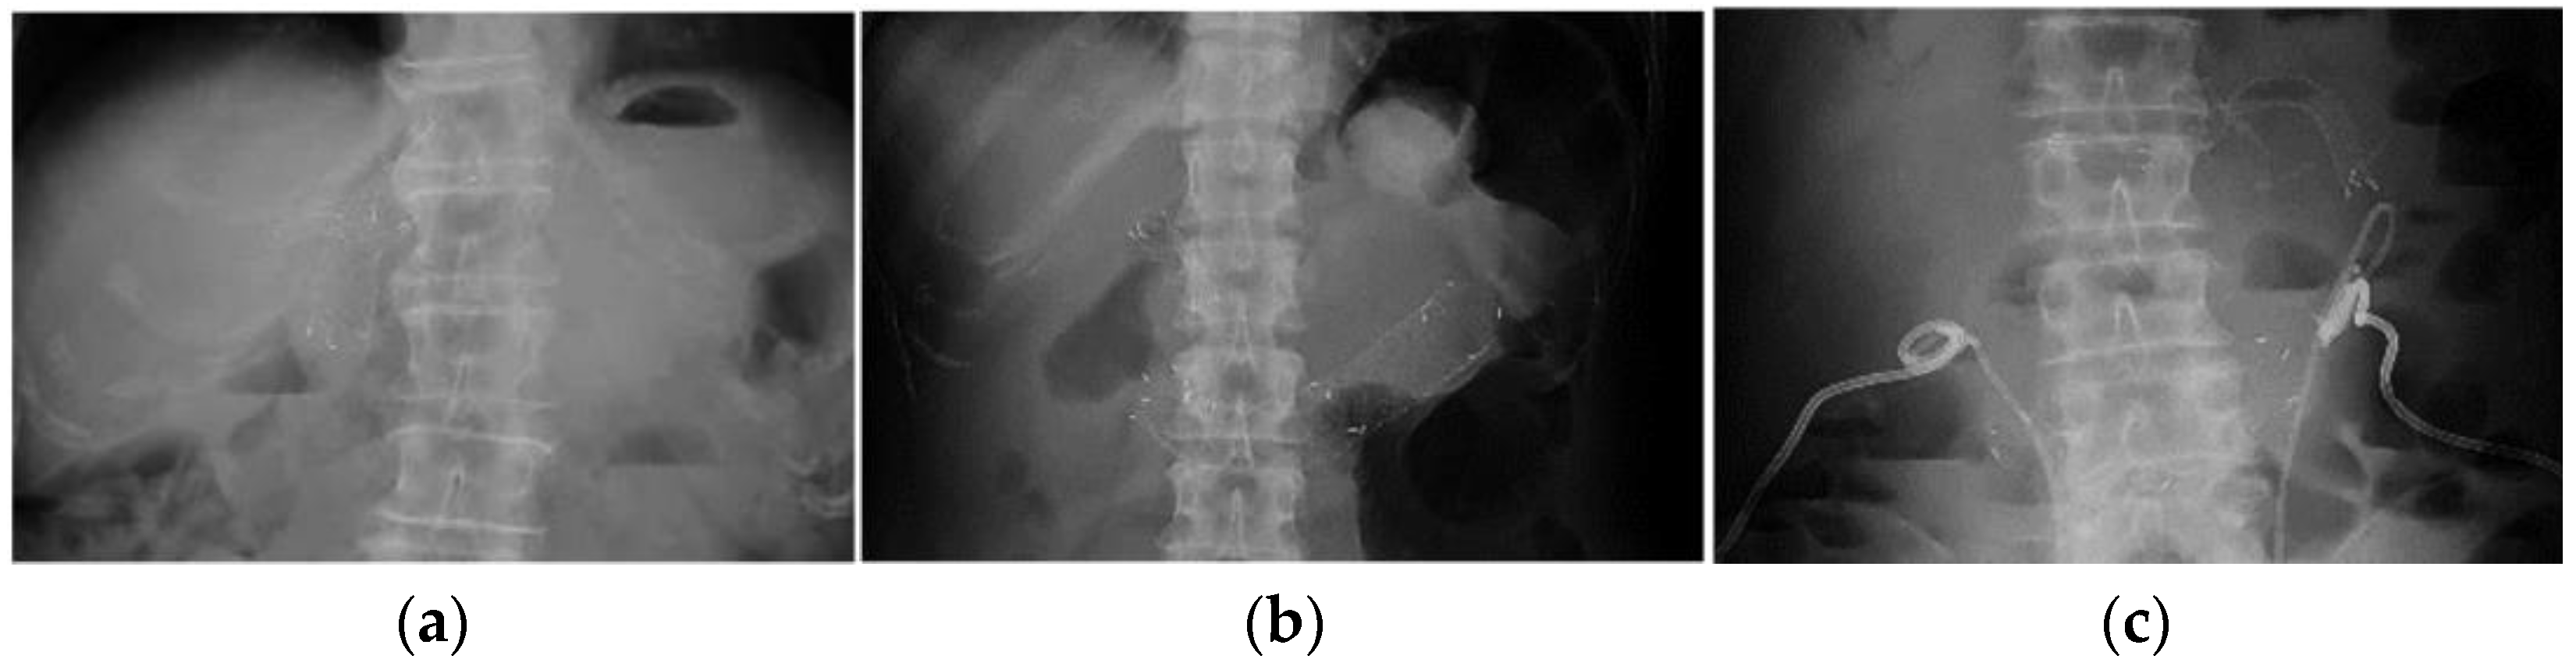

2. Materials and Methods

2.3. Endoscopic Procedure